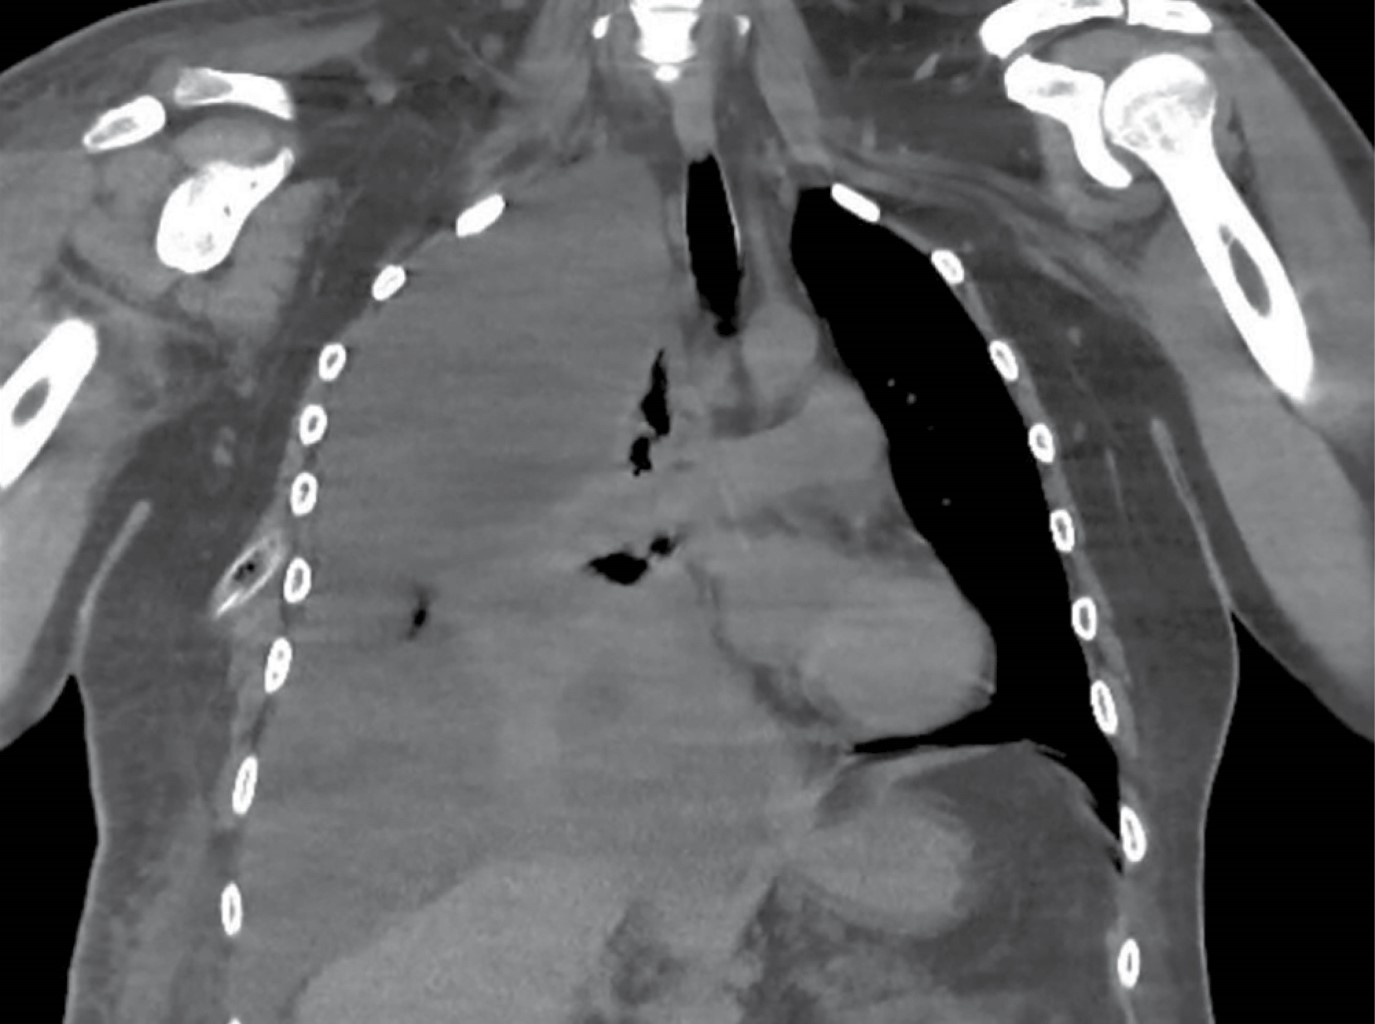

Se realizó tomografía computada simple de tórax con hallazgos de colapso pulmonar, derrame pericárdico leve, así como ganglios reactivos mediastinales (Figura 2). Se inició ajuste de dieta a base de triglicéridos de cadena larga por dos meses para disminuir la producción de quilotórax, manejo con octreótide 600 μg diarios por dos semanas y posteriormente con nutrición parenteral al no presentar mejoría. A las tres semanas se agrega salida de material purulento por sonda de drenaje pleural; se opta por manejo con aseo quirúrgico y ligadura de conducto torácico en bloque con decorticación pleural derecha por parte del Servicio de Cirugía de Tórax. Se evidenció derrame pleural de quilo aproximadamente de tres litros con presencia de adherencias laxas entre pleura parietal y visceral, engrosamiento pleural variable desde 2 hasta 5 mm y un conducto torácico dilatado de aproximadamente 7 mm. Posterior al procedimiento con éxito y adecuada reexpansión, se procedió a realización de pleurodesis química con yodopovidona en tres ocasiones a lo largo de su hospitalización.